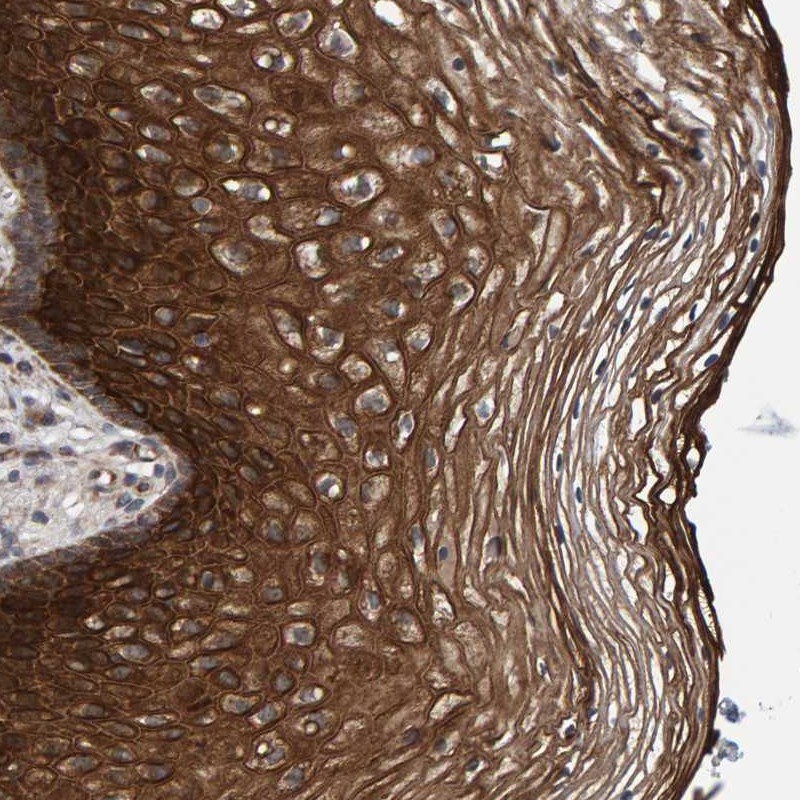

Immunohistochemical staining of human vagina shows strong cytoplasmic positivity in squamous epithelial cells.